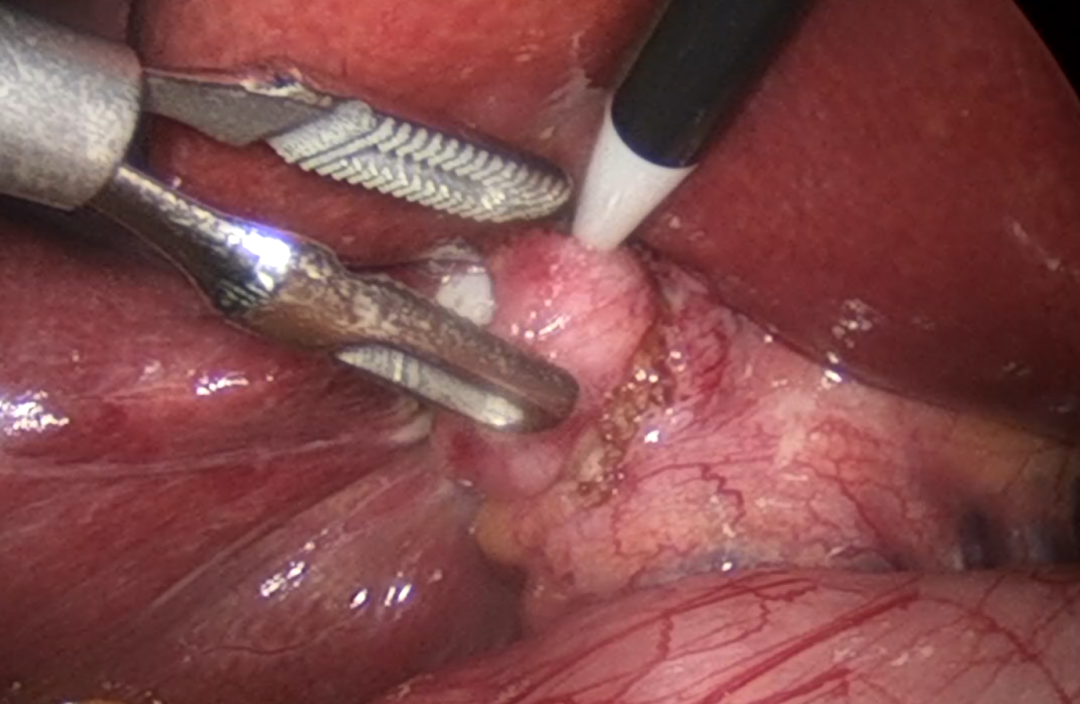

手术在全身麻醉下进行。正如术前所料,腹腔镜探查发现,患者胆囊已严重萎缩、壁厚、失去正常形态,与肝脏、胆总管及周围组织形成致密瘢痕粘连,胆囊三角区解剖结构完全被坚硬的纤维瘢痕组织所覆盖和封闭,分离异常困难。在主任医师的稳健操作下,手术团队犹如在“雷区”中精细排雷,利用腹腔镜的放大视野和超声刀等先进器械,以极大的耐心和精准的手法,一点一点地分离瘢痕组织,仔细辨识并保护肝总管、胆总管及重要血管,历经数小时,最终安全地完成了萎缩胆囊的完整切除,成功化解了手术的第一大难关。

图片

紧接着,团队转而处理胆总管问题。切开胆总管后,发现其内存在多枚大小不等的结石。由于结石较多,且部分可能与管壁有粘连,取石过程需要格外细致。手术团队运用专业的胆道镜和取石器械,在镜下反复探查、抓取、冲洗,确保将所有结石,特别是位于肝内胆管可能存在的结石,悉数取净。在确认胆道系统畅通无阻后,于胆总管内精准放置T型引流管并妥善缝合固定。整个手术过程虽艰难曲折,但团队配合默契,操作稳健,成功控制了出血,未发生胆道损伤等严重并发症。